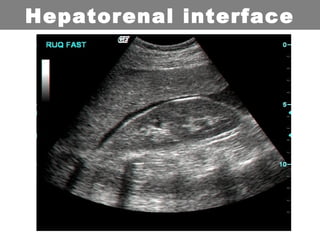

Scans are obtained at 4 interfaces:

•Hepatorenal interface

Hepatorenal interface

• FAST scan:

– Free fluids in the hepatorenal interface